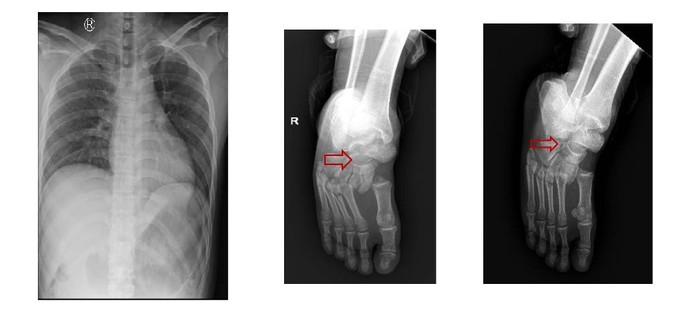

Kết quả chụp X-quang ngực thẳng, cổ bàn chân phải của các bệnh nhân. (Ảnh: Bệnh viện cung cấp)

2 bệnh nhân nam nhập viện trong tình trạng đau đớn, liệt hoàn toàn 2 chân, bí tiểu… Khai thác bệnh sử, trong lúc nam bệnh nhân 28 tuổi, quê ở Hải Dương, đang sửa cáp thang máy thì người đồng nghiệp (26 tuổi, quê Tiền Giang) bước vào thang khiến thang quá tải rơi xuống từ lầu 7.